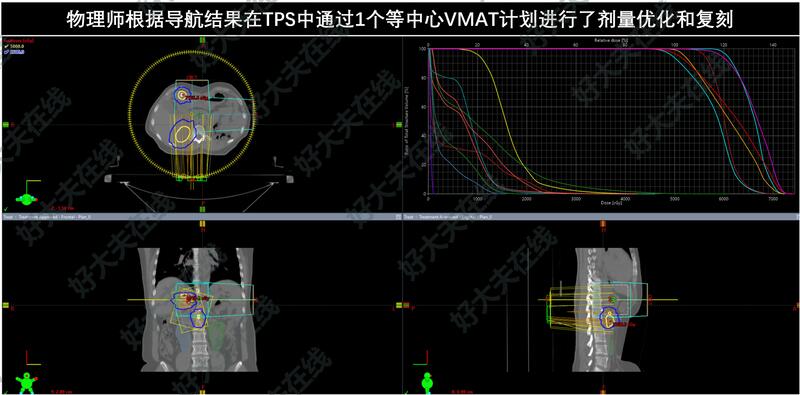

但患者有3个病灶(肝内2病灶+腹膜后淋巴结),3病灶最大径依次为1.7cm,4.3cm和5.1cm,都不同程度的靠近辐射敏感的胃肠道关键脏器,且患者肝脏术后体积仅1022.6ml。如何至少达到80Gy以上的BED10以获得对病灶的良好局控,同时让肝脏和胃肠道的辐射损伤在可以耐受的范围内,是该患者治疗成功的关键。

对这种疑难的多病灶放疗,经过谨慎的剂量学评估后,最终对3个病灶分别处方SBRT放疗50Gy/8Fx。小肠、结肠和胃均有极小体积的高剂量超标,但在临床可接受范围之内。

患者于2023年8月完成SBRT放疗:50Gy/8Fx(处方BED=81.3Gy,3个PTV内平均BED依次为112.6Gy,107.5Gy,96.4Gy)。